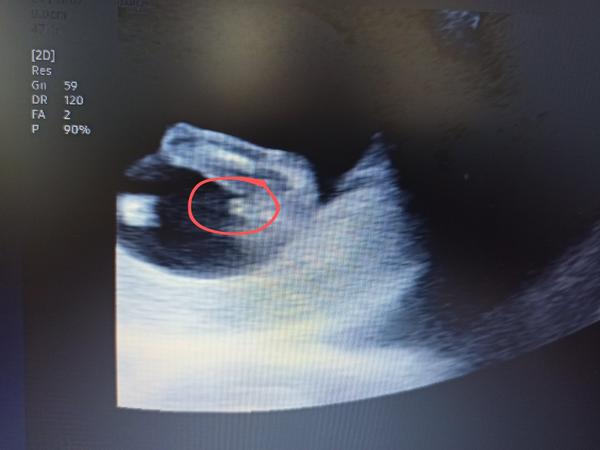

Dobrý den, oživuji diskuzi ❤️ 11tt, je to jen screenshot z videa které jsem si natočila na mobil, tak bůh ví, zda jsem to cvakla v dobrou chvíli a není to klamavé 😄 Co myslíte? Do prenatalu jdeme až 6.11. a já mám pocit že prasknu nedočkavostí, jsem zvědavec hrozný 🙈 Toť otázka - pohlavní hrbolek, nebo jsou to kulky, nebo konec kostrče? Co myslíte, jen tak pro srandu? Přáli bychom si holku, ale kdyz jsem videla prvni pohyby na UTZ v 11+1, tak jsem si uvědomila že ať bude co bude, budu mimi milovat uplne stejne bez rozdílu ❤️ Je to mazec!!